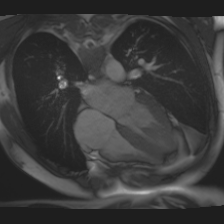

Accurate segmentation and motion estimation of myocardium have always been important in clinic field, which essentially contribute to the downstream diagnosis. However, existing methods cannot always guarantee the shape integrity for myocardium segmentation. In addition, motion estimation requires point correspondence on the myocardium region across different frames. In this paper, we propose a novel end-to-end deep statistic shape model to focus on myocardium segmentation with both shape integrity and boundary correspondence preserving. Specifically, myocardium shapes are represented by a fixed number of points, whose variations are extracted by Principal Component Analysis (PCA). Deep neural network is used to predict the transformation parameters (both affine and deformation), which are then used to warp the mean point cloud to the image domain. Furthermore, a differentiable rendering layer is introduced to incorporate mask supervision into the framework to learn more accurate point clouds. In this way, the proposed method is able to consistently produce anatomically reasonable segmentation mask without post processing. Additionally, the predicted point cloud guarantees boundary correspondence for sequential images, which contributes to the downstream tasks, such as the motion estimation of myocardium. We conduct several experiments to demonstrate the effectiveness of the proposed method on several benchmark datasets.